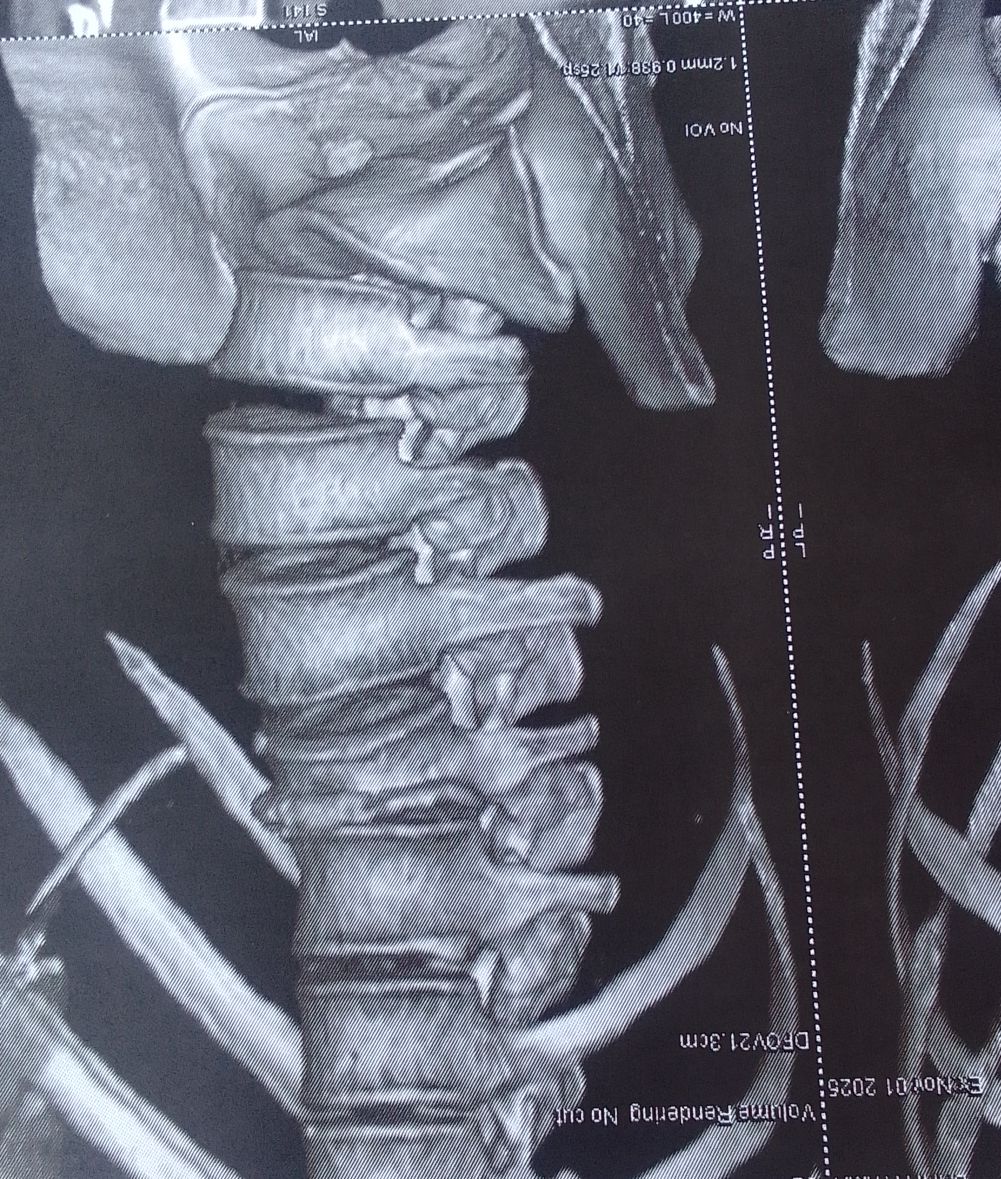

كسر في فقرات الظهر ولا يوجد تنمل في الارجل ولا شلل

كسر في فقرات الظهر ولا يوجد تنمل في الارجل ولا شلل هل تحتاج الى جراحة وما نوع الجراحة ادا امكن

كسر انضغاطي من الدرجة الثالثة ، وهو كسر غير ثابت، يحتاج الى جراحة لرد الكسر وتثبيت الفقرات. والف سلامة ولابد من عمل رنين مغناطيسي قبل اجراء الجراحة 0 2025-11-12T12:07:58+00:00 2025-11-12T12:07:58+00:00

كسر انضغاطي من الدرجة الثالثة ، وهو كسر غير ثابت، يحتاج الى جراحة لرد الكسر وتثبيت الفقرات. والف سلامة ولابد من عمل رنين مغناطيسي قبل اجراء الجراحة